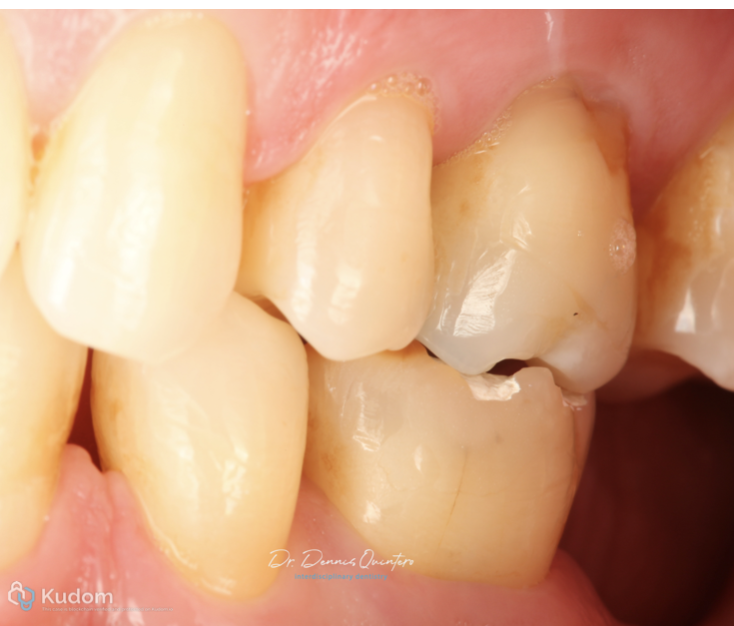

Fig. 2

Initial clinical situation

Fig. 3

. Tooth 3.6 with irreversible pulpitis.

. Occlusal structural loss.